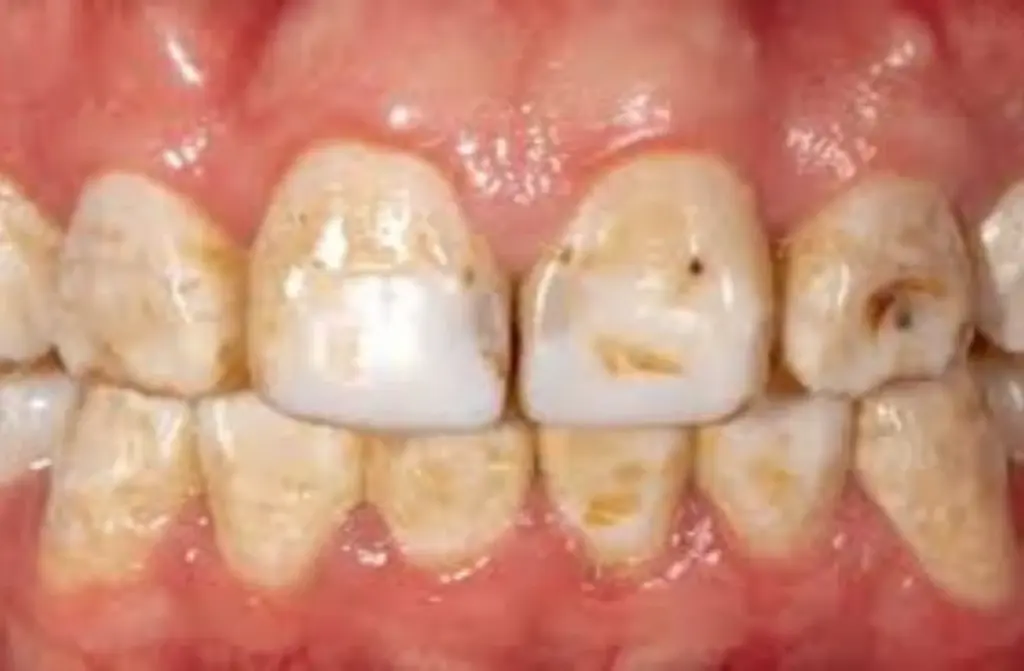

- Moderate Fluorosis: Brown or yellowish stains that are more apparent, affecting a larger portion of the enamel.

- Severe Fluorosis: Pronounced staining with possible pitting and rough enamel texture.